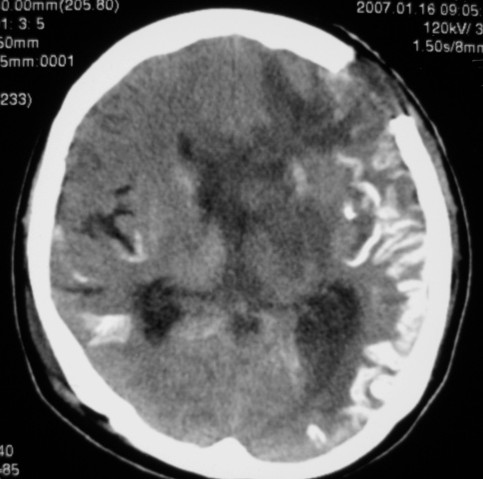

标题: CT9218:男性,50岁,脑出血术后复查,两次片相隔半月,请分 [打印本页]

标题: CT9218:男性,50岁,脑出血术后复查,两次片相隔半月,请分

第一次ct片脑出血术后,出血吸收期。第二次ct 片左颞顶枕部及右颞顶部有脑回样高密度影。考虑珠网膜下腔出血。脑出血术后改变,脑出血恢复期 并脑积水。

脑炎;脑出血术后改变;脑积水。

考虑脑膜感染后的改变,术后改变。

我觉得大家说得都对,我看不懂这个片子。除了各位老师的意见之外,我是像有无可能是这样呢:由于外伤后脑组织损伤,相对于外伤前,脑组织可能处于缺血状态,所以脑回的强化可否用脑缺血(相当于脑梗塞后脑回样强化)后的脑回样强化来解释呢。